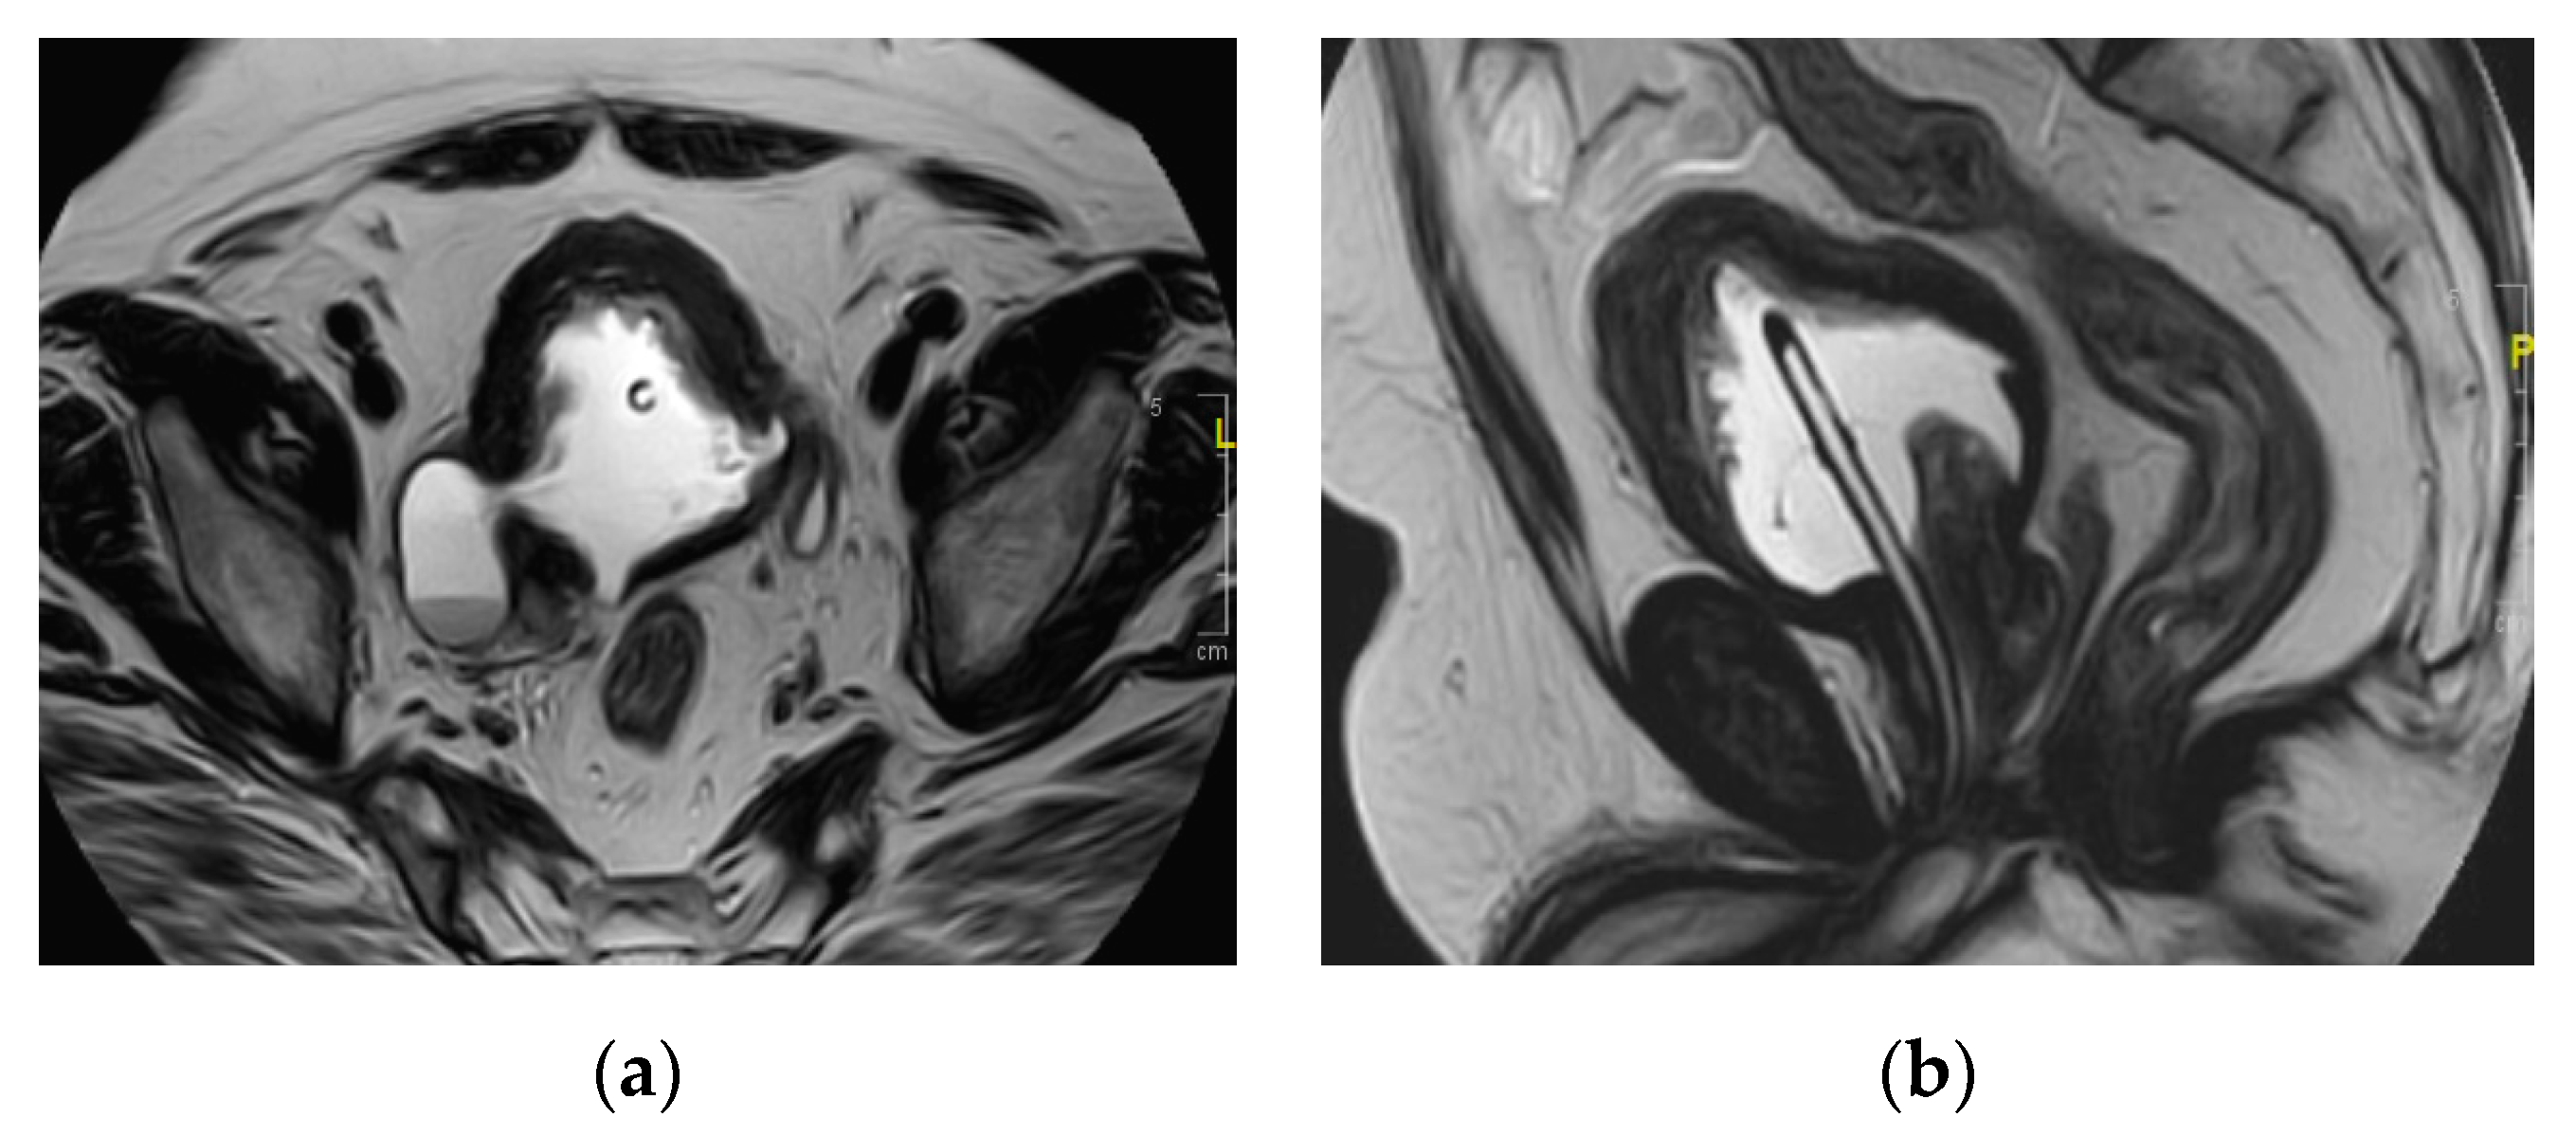

2.15. Acute Bacterial Prostatitis and Prostatic Abscess

| Prostatic abscess | Non enhancing fluid collection with peripheral or septal enhancement and non-enhancing central fluid. Possible extraprostatic extension |